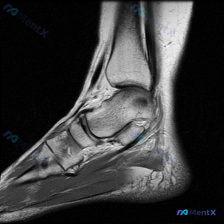

刚看到一个很有代表性的读片病例,临床怀疑膝关节软骨异常,给了单幅膝关节矢状位T2加权MRI,整理一下分析思路分享给大家。 病例基本信息 - 临床问题:标识图像显示的异常是否为软骨异常 - 影像资料:单幅膝关节矢状位T2加权(或脂肪抑制质子密度加权)MRI,图像质量好,无运动伪影,覆盖股骨远端、胫骨近...